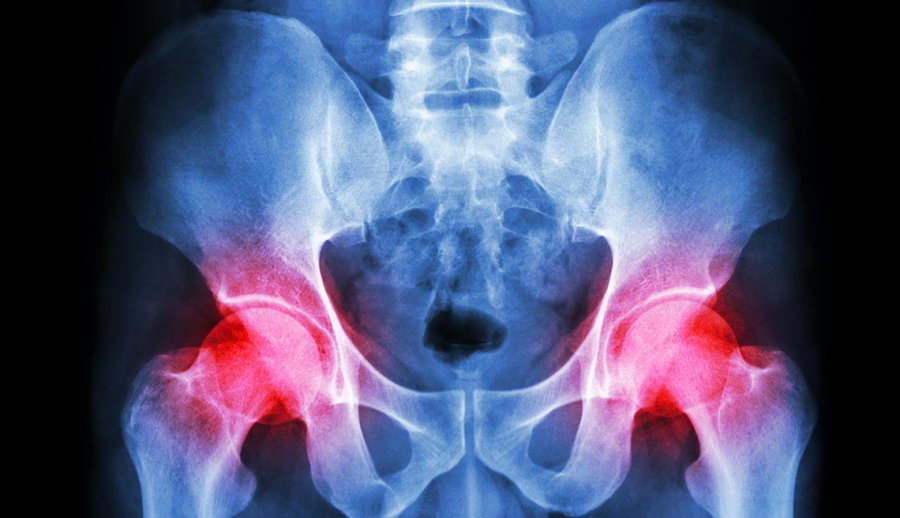

22+ Bone On Bone Hip Surgery Pictures

22+ Bone On Bone Hip Surgery Pictures. Even if you have an mri that shows complete bone on bone, you might not need surgery. Joint replacement is not the only possible answer.sterling structural.

Cheap medical science, buy quality education & office supplies directly from china suppliers:orthopedic surgery simulation sawbone artificial bone artificial iliac bone hip model enjoy free shipping worldwide! Prior to puberty, the these can be 'unstable' injuries and may require urgent surgery. If the hips or spine are involved, the injections usually are. Considering hip replacement surgery for osteoarthritis?